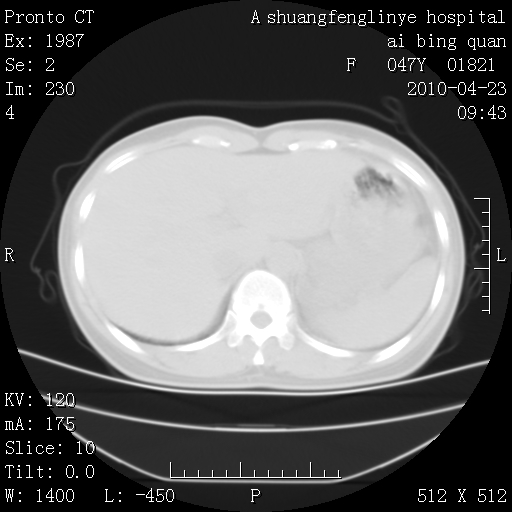

标题: CT25944:胸痛、气短、前几日高烧!肺Ca?请会诊!

双肺多发结节,考虑转移瘤,肺癌肺转移不除外

双肺多发结节,部分密度较高,最大结节边缘光滑。临床有“胸痛、气短、前几日高烧”病史。首选考虑:右肺感染性病变!建议积极消炎后复查!